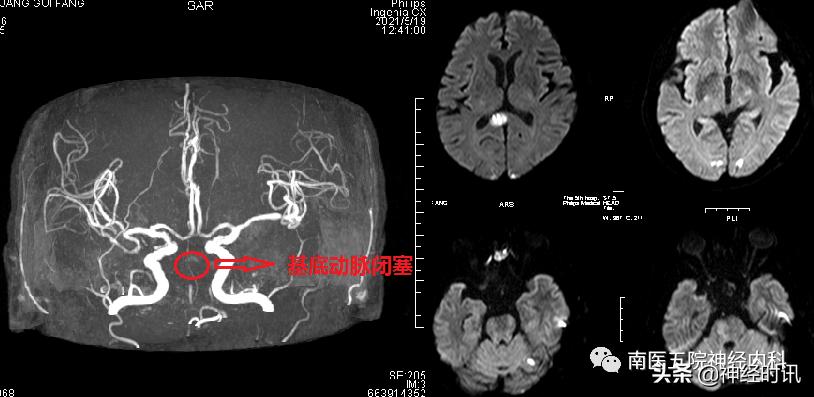

神内医生王亚军医师赶到后查看患者并结合其检查,诊断明确,就是脑梗塞,并且是基底动脉大血管梗塞,但症状却非常不典型,诊断困难,只有通过影像学检查才能明确,并且该动脉闭塞很是凶险,即使积极救治,其后期残疾或死亡的风险仍接近 80% ,也就是患者随时有致残或危及生命的可能,建议转神经内科积极治疗,心内科医生一刻也不敢耽误,立即办理转科流程,转入神经内科后查体患者言语变得不清,一侧肢体也变得没有力了,患者病情在逐渐加重,因是大血管堵塞,建议积极行介入手术治疗,开通堵塞的血管,该手术创伤小、出血少、疼痛轻、恢复快,但也有一定的风险,家属慎重考虑后同意手术治疗,我科遂联系导管室、麻醉科医师及神经介入手术相关人员行手术治疗。术中造影明确血管闭塞部位,全麻后,经积极的首过效应并给予单纯球囊扩张成形术后闭塞血管再通,且远端血管 血流充盈良好,观察十分钟后再次造影远端血流依然充盈良好,结束手术。